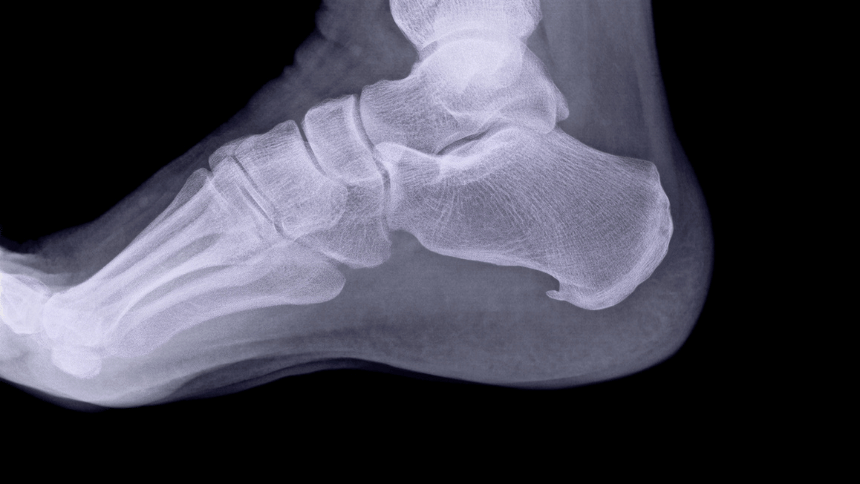

Diagnostika zahrnuje fyzické vyšetření nohy a dotazy na typ zátěže, která mohla bolest vyvolat. K úplnému potvrzení diagnózy se často využívá rentgen, na němž je ostruha dobře viditelná.